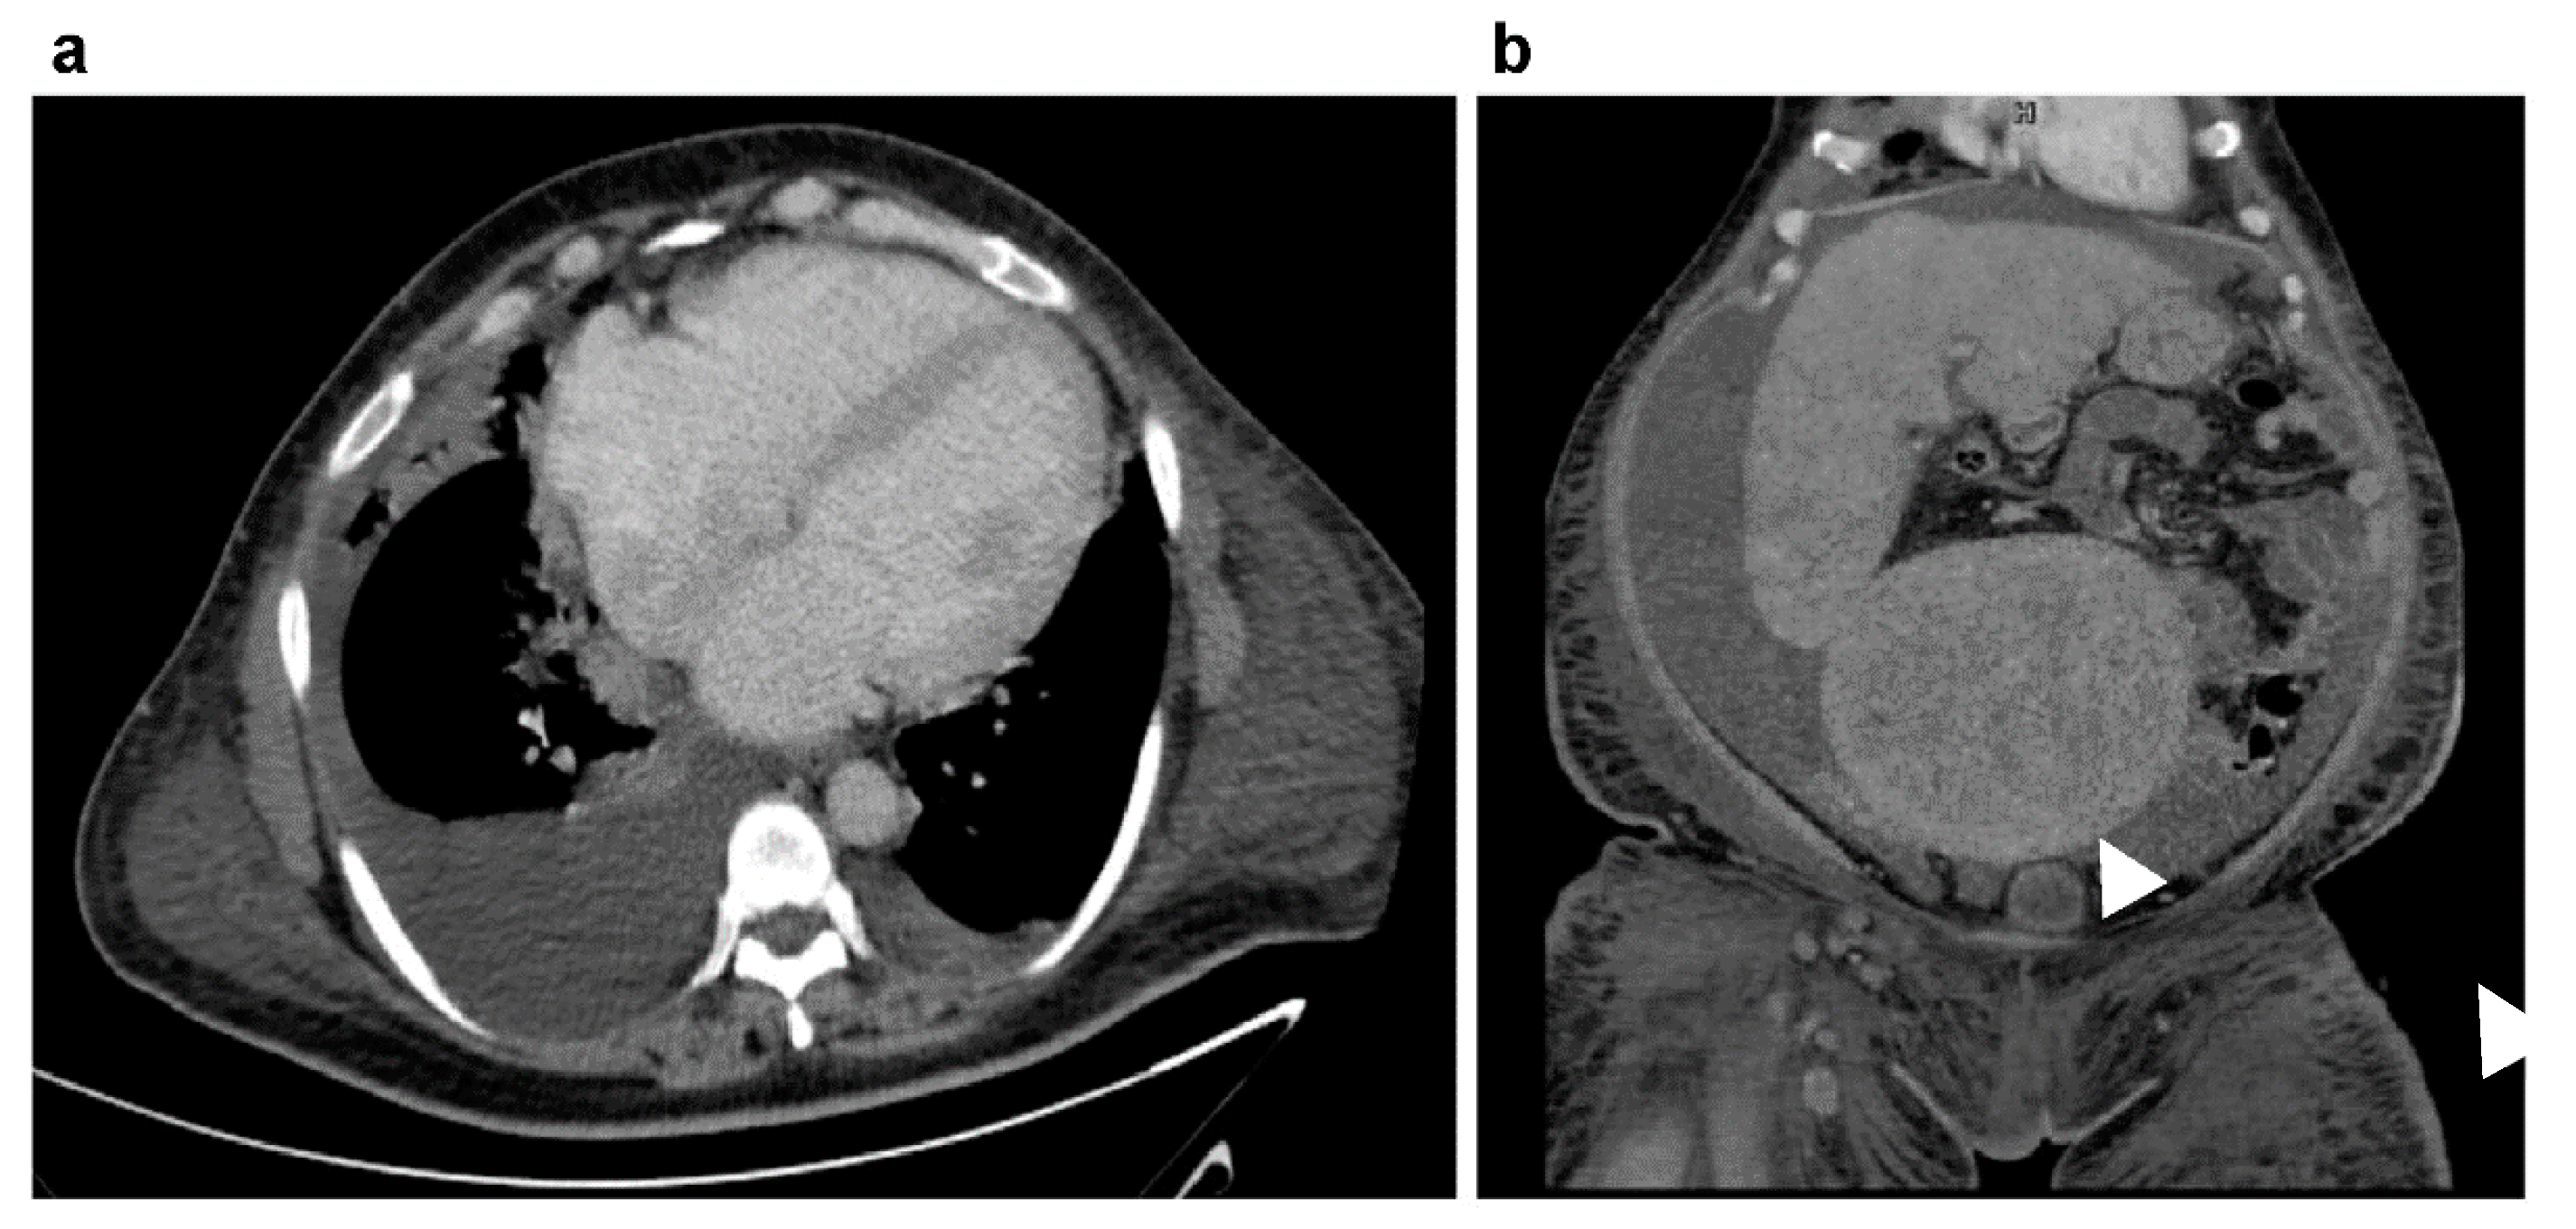

2. Case Presentation